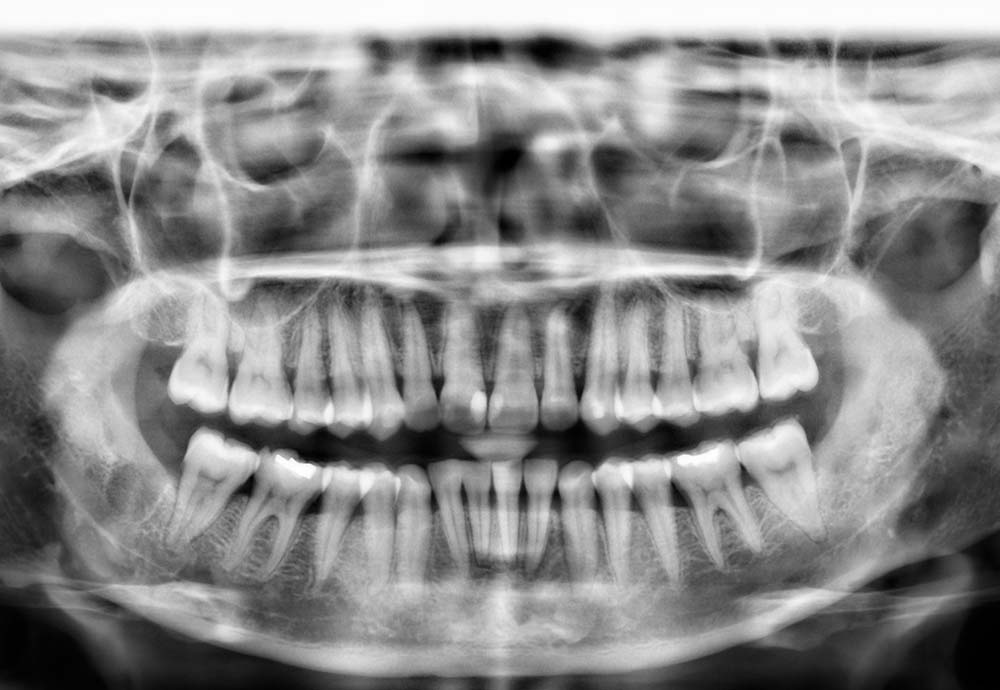

Wisdom teeth may need to be removed if they are impacted, causing pain, swelling, infection, or damage to nearby teeth.

Other reasons include preventing future dental problems such as decay, gum disease, cysts, or crowding of your existing teeth.